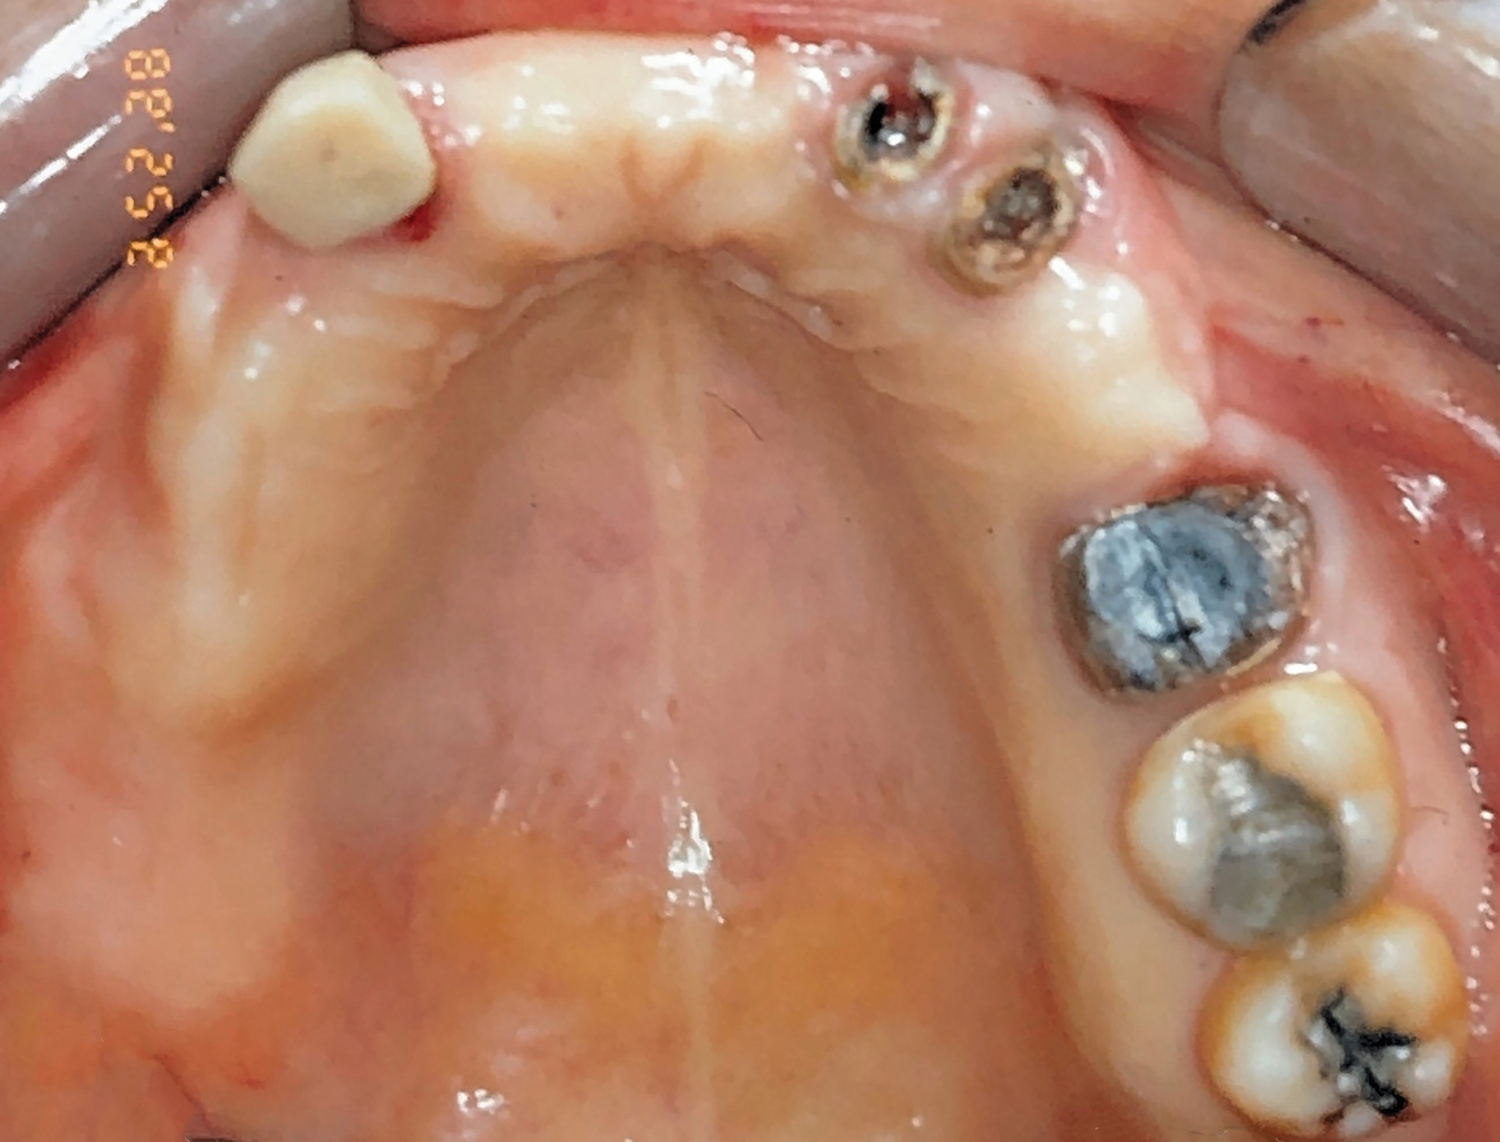

Fig 1. Initial occlusal view of maxillary arch.

Figure 1

Clinical and radiographic examinations were carried out and revealed multiple missing teeth, nonrestorable teeth, periodontal disease, and bone loss (Figure 1 and Figure 2). The final treatment plan that was then proposed to and accepted and signed by the patient included extraction of all remaining teeth in the maxilla, delivery of a provisional fixed restoration supported by six transitional implants, bilateral sinus augmentation, placement of eight to 10 conventional implants, and an implant-supported porcelain-fused-to-metal or hybrid (screw-retained) restoration. For the mandible, the plan included extraction of teeth Nos. 29 and 32 and placement of implants in sites Nos. 18, 19, 20, 29, 30, and 31, with three splinted implant-supported fixed crowns on each side. The patient, however, decided to proceed only with the maxillary restoration and have the mandibular implants and restorations done in private practice.